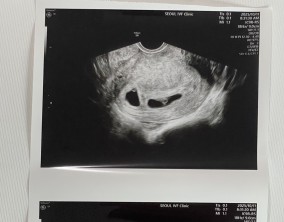

심장소리 이후, 함께 웃게 된 임밍아웃